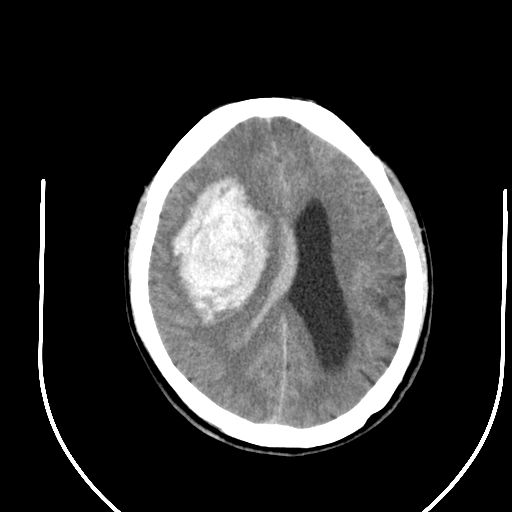

标题: CT24997:M,60Y,突发昏迷30分钟,有高血压病史。 [打印本页]

标题: CT24997:M,60Y,突发昏迷30分钟,有高血压病史。

右侧基底节区脑出血并破溃入脑室。

支持楼主诊断,脑中线结构有偏移,脑疝形成可能!

1右侧基底节脑出血伴脑干出血并破入脑室系统脑疝形成2梗阻性脑积水

1)右侧基底节脑出血伴脑干出血并破入脑室系统。2)大脑镰下疝。3)梗阻性脑积水。

1、右侧基底节脑出血伴脑干出血并破入脑室系统。

2、大脑镰下疝。

3、梗阻性脑积水。